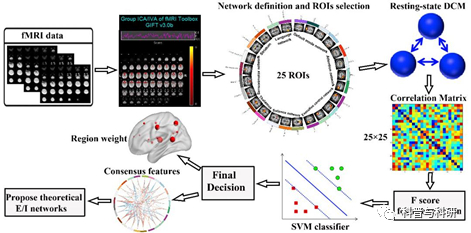

多指标融合分类诊断 |

1、基于多指标疾病分类/诊断的原理 2、LASSO特征选择 3、MultiKernel SVM分类的基本原理 4、代码解读 5、代码实操练习 |

基于功能连接矩阵的SVM分类 |

1、基于功能连接矩阵的SVM分类基本原理+流程介绍 2、相关高质量文章介绍 3、代码解读 4、代码实操练习 |